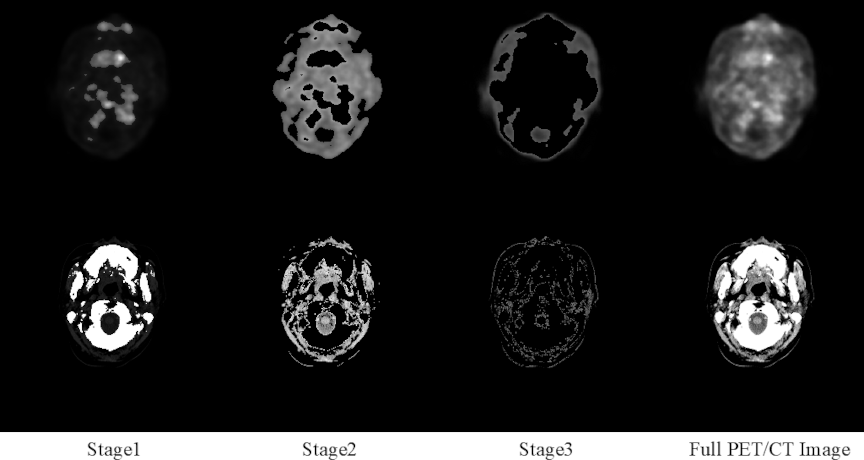

To address distinct optimization tasks effectively, the triple-stage generator employs a mirror-symmetry arrangement of encoders and decoders (Fig. 3). Three encoder–decoder pairs—each comprising an encoder, decoder, skip connections, and Visualized Block—sequentially produce outputs labeled Stage1, Stage2, and Output. Each output is used for dedicated loss computations, facilitating focused improvements in structural constraints, texture fidelity, and final image adjustment.

Fig. 4. Triple-stage generator architecture. It comprises three identical encoder–decoder modules (shown as colored sections). “Stage1,” “Stage2,” and “Output” denote the outputs of the first, second, and third generators, respectively. The arrows leading from each output indicate the loss functions applied to that particular output.

This multistage division of structural, textural, and synthesis tasks is advantageous in handling multiobjective optimization, offering a clearer pathway for tackling precision bottlenecks often encountered in single-stage cross-modal medical image translation. Fig. 4 illustrates the overall network design explained hereunder:

Hierarchical Learning Advantage: The triple-stage generator consists of three collaboratively operating sub-modules:

Stage 1–Structural Constrainer: Captures and reinforces the overall anatomical layout, ensuring the accuracy of the macro-structure.

Stage 2–Texture Refiner: Further enriches tissue textures and edge fidelity on the structurally coherent basis established in Stage 1.

Stage 3–Fusion Synthesizer: Integrates multi-scale features from the preceding stages to harmonize structure and texture in the final output.

Model Interpretability: This study employed a streamlined encoder–decoder architecture. Multistage cascade experiments of up to four stages revealed that the three-stage variant achieved the best overall performance. Building upon this observation, we introduced a brightness-sensitive loss function that decomposes the cross-modal translation task into three brightness-weighted subtasks, enabling each generator to focus on a specific high-priority region, as illustrated in Fig. 12.

The first row of Fig. 12 presents the original PET image and its three segmented regions obtained via thresholding within the brightness-sensitive loss. The second row shows the corresponding original CT image and its segmented regions. Conceptually, this design parallels partitioning a style-transfer problem into three brightness-defined regions, processed sequentially by three generators, each dedicated to a distinct focus area. The synergistic integration of the brightness-sensitive loss with the multistage generator not only improves quantitative accuracy but also substantially enhances the interpretability of the entire framework.